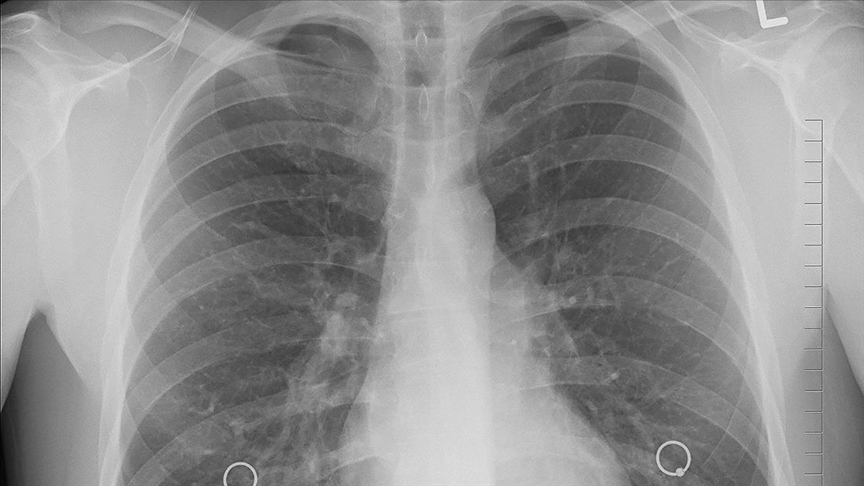

Kistik fibrozis (KF), doğumdan itibaren solunum sistemi, sindirim sistemi ve üreme sistemininde yer alan mukus ve ter bezlerini etkileyen kalıtsal bir hastalıktır. Kistik Fibrozis özellikle, akciğerler, pankreas, karaciğer, bağırsaklar, sinüsler ve cinsel organların işlevini önemli derecede etkilemektedir.

Kistik fibrozis hastalığına sahip kişilerde, vücuttaki yer alan mukus kalınlaşır ve yapışkan bir hal alır. Bu durumda kişinin nefes almada zorlanmasına neden olur ve ciddi bir akciğer enfeksiyonu gelişme olasılığını artırır.